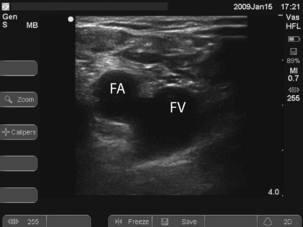

To locate the vein, introduce the needle 1 cm medial to the femoral artery close to the inguinal ligament. It is a common mistake to go too low where the superficial femoral artery overlies the vein. Long catheters, 24 cm plus, are required to get the tip of the catheter into the IVC, which may be required for good flows (e.g. for dialysis).

To locate the vein, introduce the needle 1 cm medial to the femoral artery close to the inguinal ligament. It is a common mistake to go too low where the superficial femoral artery overlies the vein. Long catheters, 24 cm plus, are required to get the tip of the catheter into the IVC, which may be required for good flows (e.g. for dialysis). Ultrasound can be used to identify the vessels and ensure that the vein is punctured near the inguinal ligament where the artery and vein lie side by side. See Fig. 15.3.

Ultrasound can be used to identify the vessels and ensure that the vein is punctured near the inguinal ligament where the artery and vein lie side by side. See Fig. 15.3.Procedure